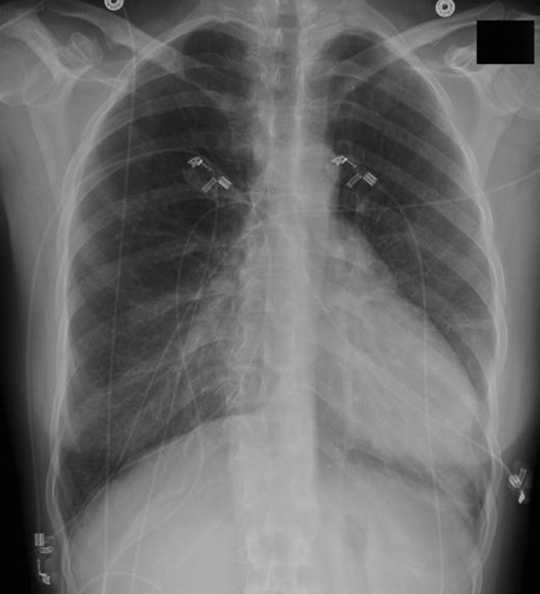

19¼¼ ³²È¯

ƯÀÌ º´·Â ¾øÀ½

¿îµ¿½Ã ÈäºÎ ºÒÆí°¨À» ÁÖ¼Ò·Î ³»¿øÇÔ.